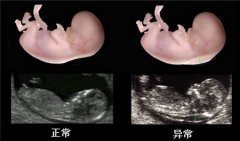

作为孕期检查项目之一NT检查 ,相信对很多孕妈妈而言,NT检查这个词还是比较陌生的...[详情]